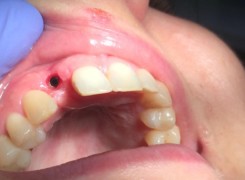

Pan Kamil zgłosił się do gabinetu po wypadku rowerowym w wyniku którego wybił ząb – lewą górną jedynkę. W takiej sytuacji została podjęta decyzja o implantacji natychmiastowej oraz zapatrzeniu pacjenta na czas integracji wszczepu w uzupełnienie tymczasowe.

Poniżej przebieg odbudowy protetycznej.